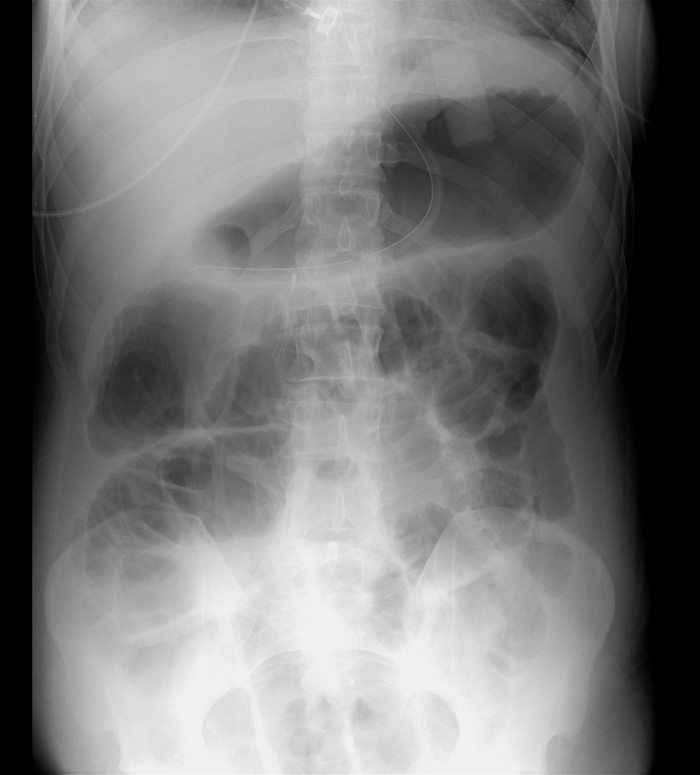

A 46-year-old man is brought to the emergency department after a fall during a downhill bicycle race.  The patient lost consciousness for approximately 1 minute and has severe back and abdominal pain.  He has no other medical conditions.  CT scan of the head reveals no intracranial bleeding; CT scan of the abdomen reveals a small retroperitoneal hemorrhage and splenic laceration.  Lumbar film suggests a compression wedge fracture of the L2 vertebral body, and a brace is placed.  The patient is conservatively managed with analgesics and supportive measures.  On hospital day 3, he has mild, diffuse abdominal pain and nausea.  His abdomen is distended, tympanic, and mildly tender without rebound or guarding.  Bowel sounds are absent.  Upright x-ray of the abdomen is shown in the image below: A 46-year-old man is brought to the emergency department after a fall during a downhill bicycle race.  The patient lost consciousness for approximately 1 minute and has severe back and abdominal pain.  He has no other medical conditions.  CT scan of the head reveals no intracranial bleeding; CT scan of the abdomen reveals a small retroperitoneal hemorrhage and splenic laceration.  Lumbar film suggests a compression wedge fracture of the L2 vertebral body, and a brace is placed.  The patient is conservatively managed with analgesics and supportive measures.  On hospital day 3, he has mild, diffuse abdominal pain and nausea.  His abdomen is distended, tympanic, and mildly tender without rebound or guarding.  Bowel sounds are absent.  Upright x-ray of the abdomen is shown in the image below:   Which of the following is the most likely diagnosis? A) Cecal volvulus B) Complete small bowel obstruction C) Gastric outlet obstruction D) Paralytic ileus E) Sigmoid volvulus F) Viscous perforation Which of the following is the most likely diagnosis?